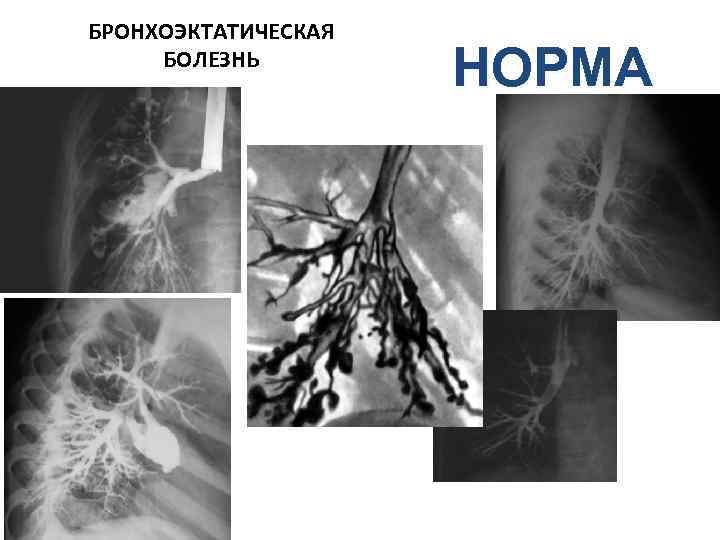

БРОНХОЭКТАТИЧЕСКАЯ БОЛЕЗНЬ НОРМА